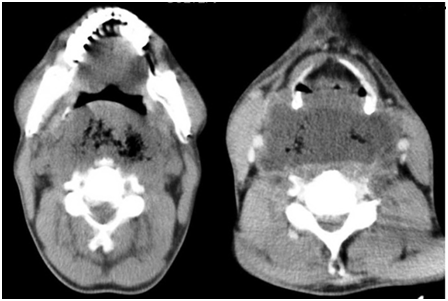

A 52year old male patient with dysphagia, sore throat, hemoptysis, cough and neck swelling referred to emergency department. He had diabetes mellitus and underwent dental filling ten days before. Physical examination revealed a swelling on the anterior pharyngeal wall. In videolaryngoscopic examination a fistula orifice and purulent discharge on the right pyriform sinus was observed (Figure 2). Neck magnetic resonance imaging (MRI) planned with retropharyngeal abscess diagnosis (Figure 3). Due to spontaneous drainage surgical intervention was not considered.

Figure 2 Drainage orifice on the right pyriform sinus, purulent drainage tot the larynx.

Figure 3 Neck MRI findings.